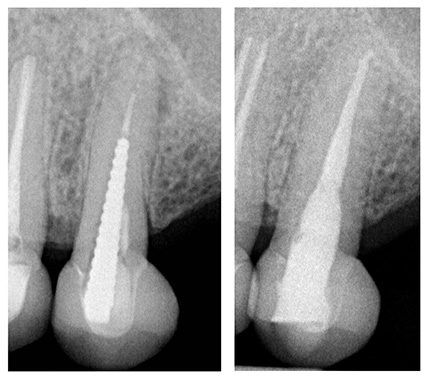

Demgegenüber stellen sehr lange Metallstifte eine deutlich höhere technische Herausforderung dar, da mit zunehmender Stiftlänge sowohl der erforderliche Substanzabtrag für die koronale Freilegung des Stiftes als auch das Risiko von Komplikationen steigen. Geschraubte Stifte können allerdings auch bei ausgedehnter Stiftlänge durch eine schallgestützte Lockerung entgegen der Einschraubrichtung vorhersagbar entfernt werden (Abb. 2a und b).

Abb. 2: a) Präoperative Einzelzahnaufnahme des Zahnes 25 mit langem geschraubtem Metallstift, b) Röntgenologische Kontrolle drei Jahre postoperativ | Fotos: Franziska Haupt